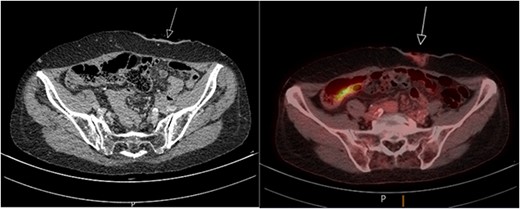

A biopsy taken from the peristomal environment revealed a cutaneous located intestinal type adenocarcinoma of colorectal origin. The subsequently performed positron emission tomography–computed tomography (PET/CT) scan showed physiological intestinal stacking and minimal fluorodeoxyglucose (FDG) stacking surrounding the colostomy site (Fig. 2). In addition, a focal hypodense thyroid nodule was found. Laboratory tests showed a stable tumor marker CEA value of 2.4 ug/L compared with a last known value of 2.3 ug/L.

PET/CT scan showing minimal FDG stacking at the colostomy site.